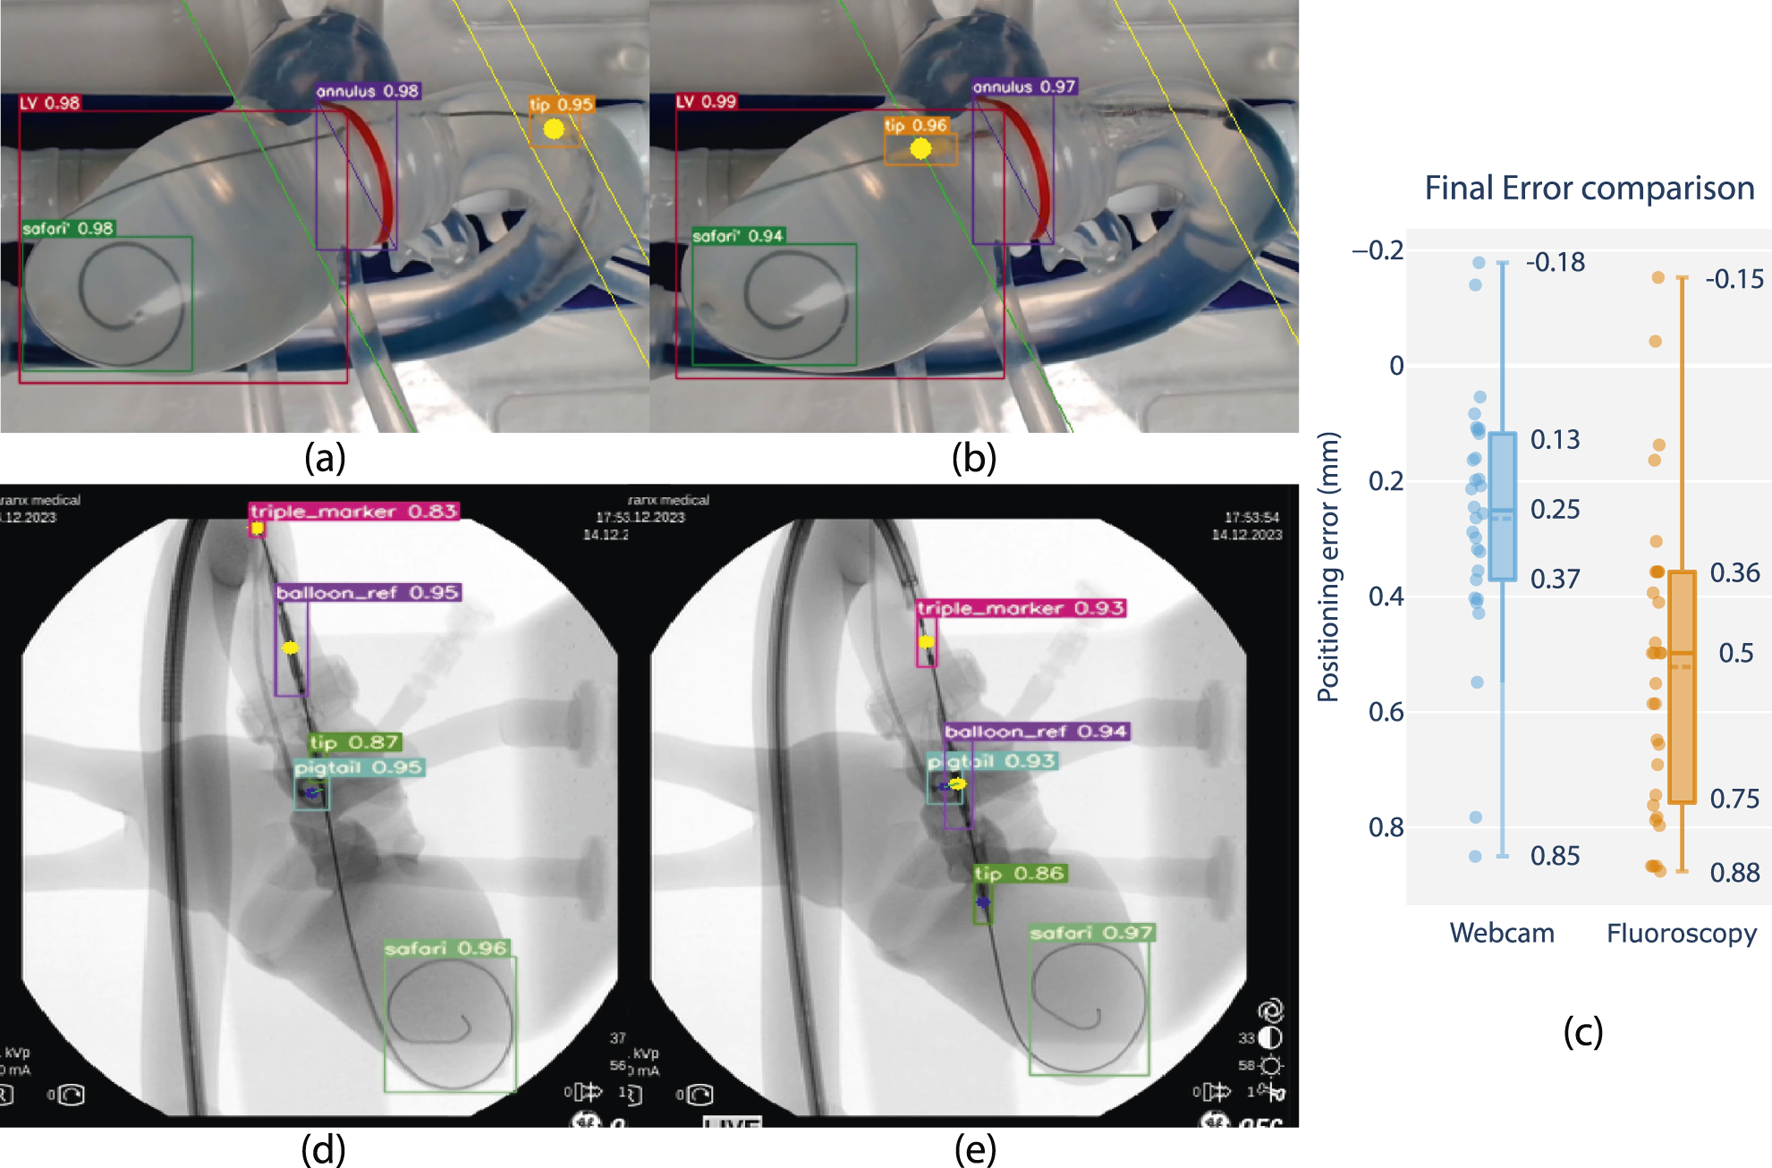

FIGURE 6

Feasibility review of closed-loop positioning using camera and fluoroscopy on phantom, comparing closed loop positioning errors. (a) Starting position and (b) final position of camera-based positioning. The balloon tip marker is pre-positioned in the ascending aorta, after which it is moved to match a planned insertion depth at a distance offset a tracked annular reference (green line). (d) Starting position and (e) final position of fluoroscopy-based positioning. The balloon reference marker is pre-positioned in the ascending aorta, after which it is positioned to match the same insertion depth as the center of a tracked pigtail reference. (c) Boxplot comparison with closed-loop positioning error performance using fluoroscopy w.r.t. the camera vision-based lab setup (in mm).*Note that fluoroscopy frames are overlayed with feature tracking and included as screen captured live on a laptop monitor display during the experiment. Raw frames are grabbed from a mobile C-arm (OEC One mobile C-Arm, GE Healthcare, Chicago, IL U.S.A.), including timestamps and other on-screen imaging parameters, and resized to a rectangular aspect ratio for visualization.

Integration and algorithm deployment was conducted on 14th of December 2023 at CERIMED Marseille. Feasibility of closed loop positioning of the delivery balloon w.r.t. a tracked anatomical target was demonstrated using fluoroscopy in a real-world end-use environment (S4). A positioning experiment was conducted 30 times with no system failure. Final positioning error is determined as 0.5 mm median error with a min-max range of 1.03 mm. When repeating the experiment using the camera vision testbench and contrasting the results, positioning performance in terms of accuracy and repeatability was demonstrated to be equivalent across imaging methods in static phantom conditions Figure 6. These observations support the claim of extending experimental observations using camera vision to a fluoroscopy setting, as well as the relevance of continued research in a non-fluoroscopy environment.